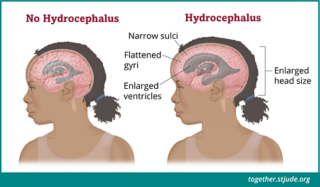

X Ray Multiple Part Of Child S Body Multiple Disease Stroke Brain Tumor Rheumatoid Arthritis Sinusitis Gouty Arthritis Etc Skull Chest Lung Heart Spine Arm Hand